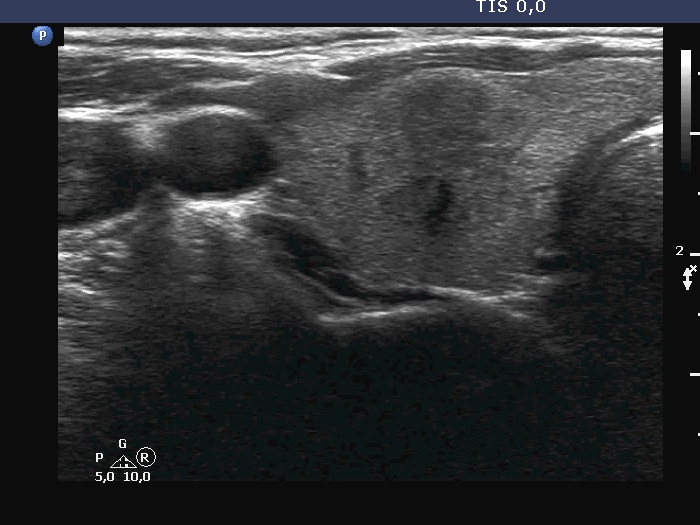

Ultrasonography. The thyroid was echonormal. There were three discrete lesions in the right lobe while several others in the left lobe. There was only one remarkable among them. This was in the ventral part of the right lobe. It was minimally hypoechoic, presented with partly irregular, partly blurred borders. Intranodular vascularity was detected.